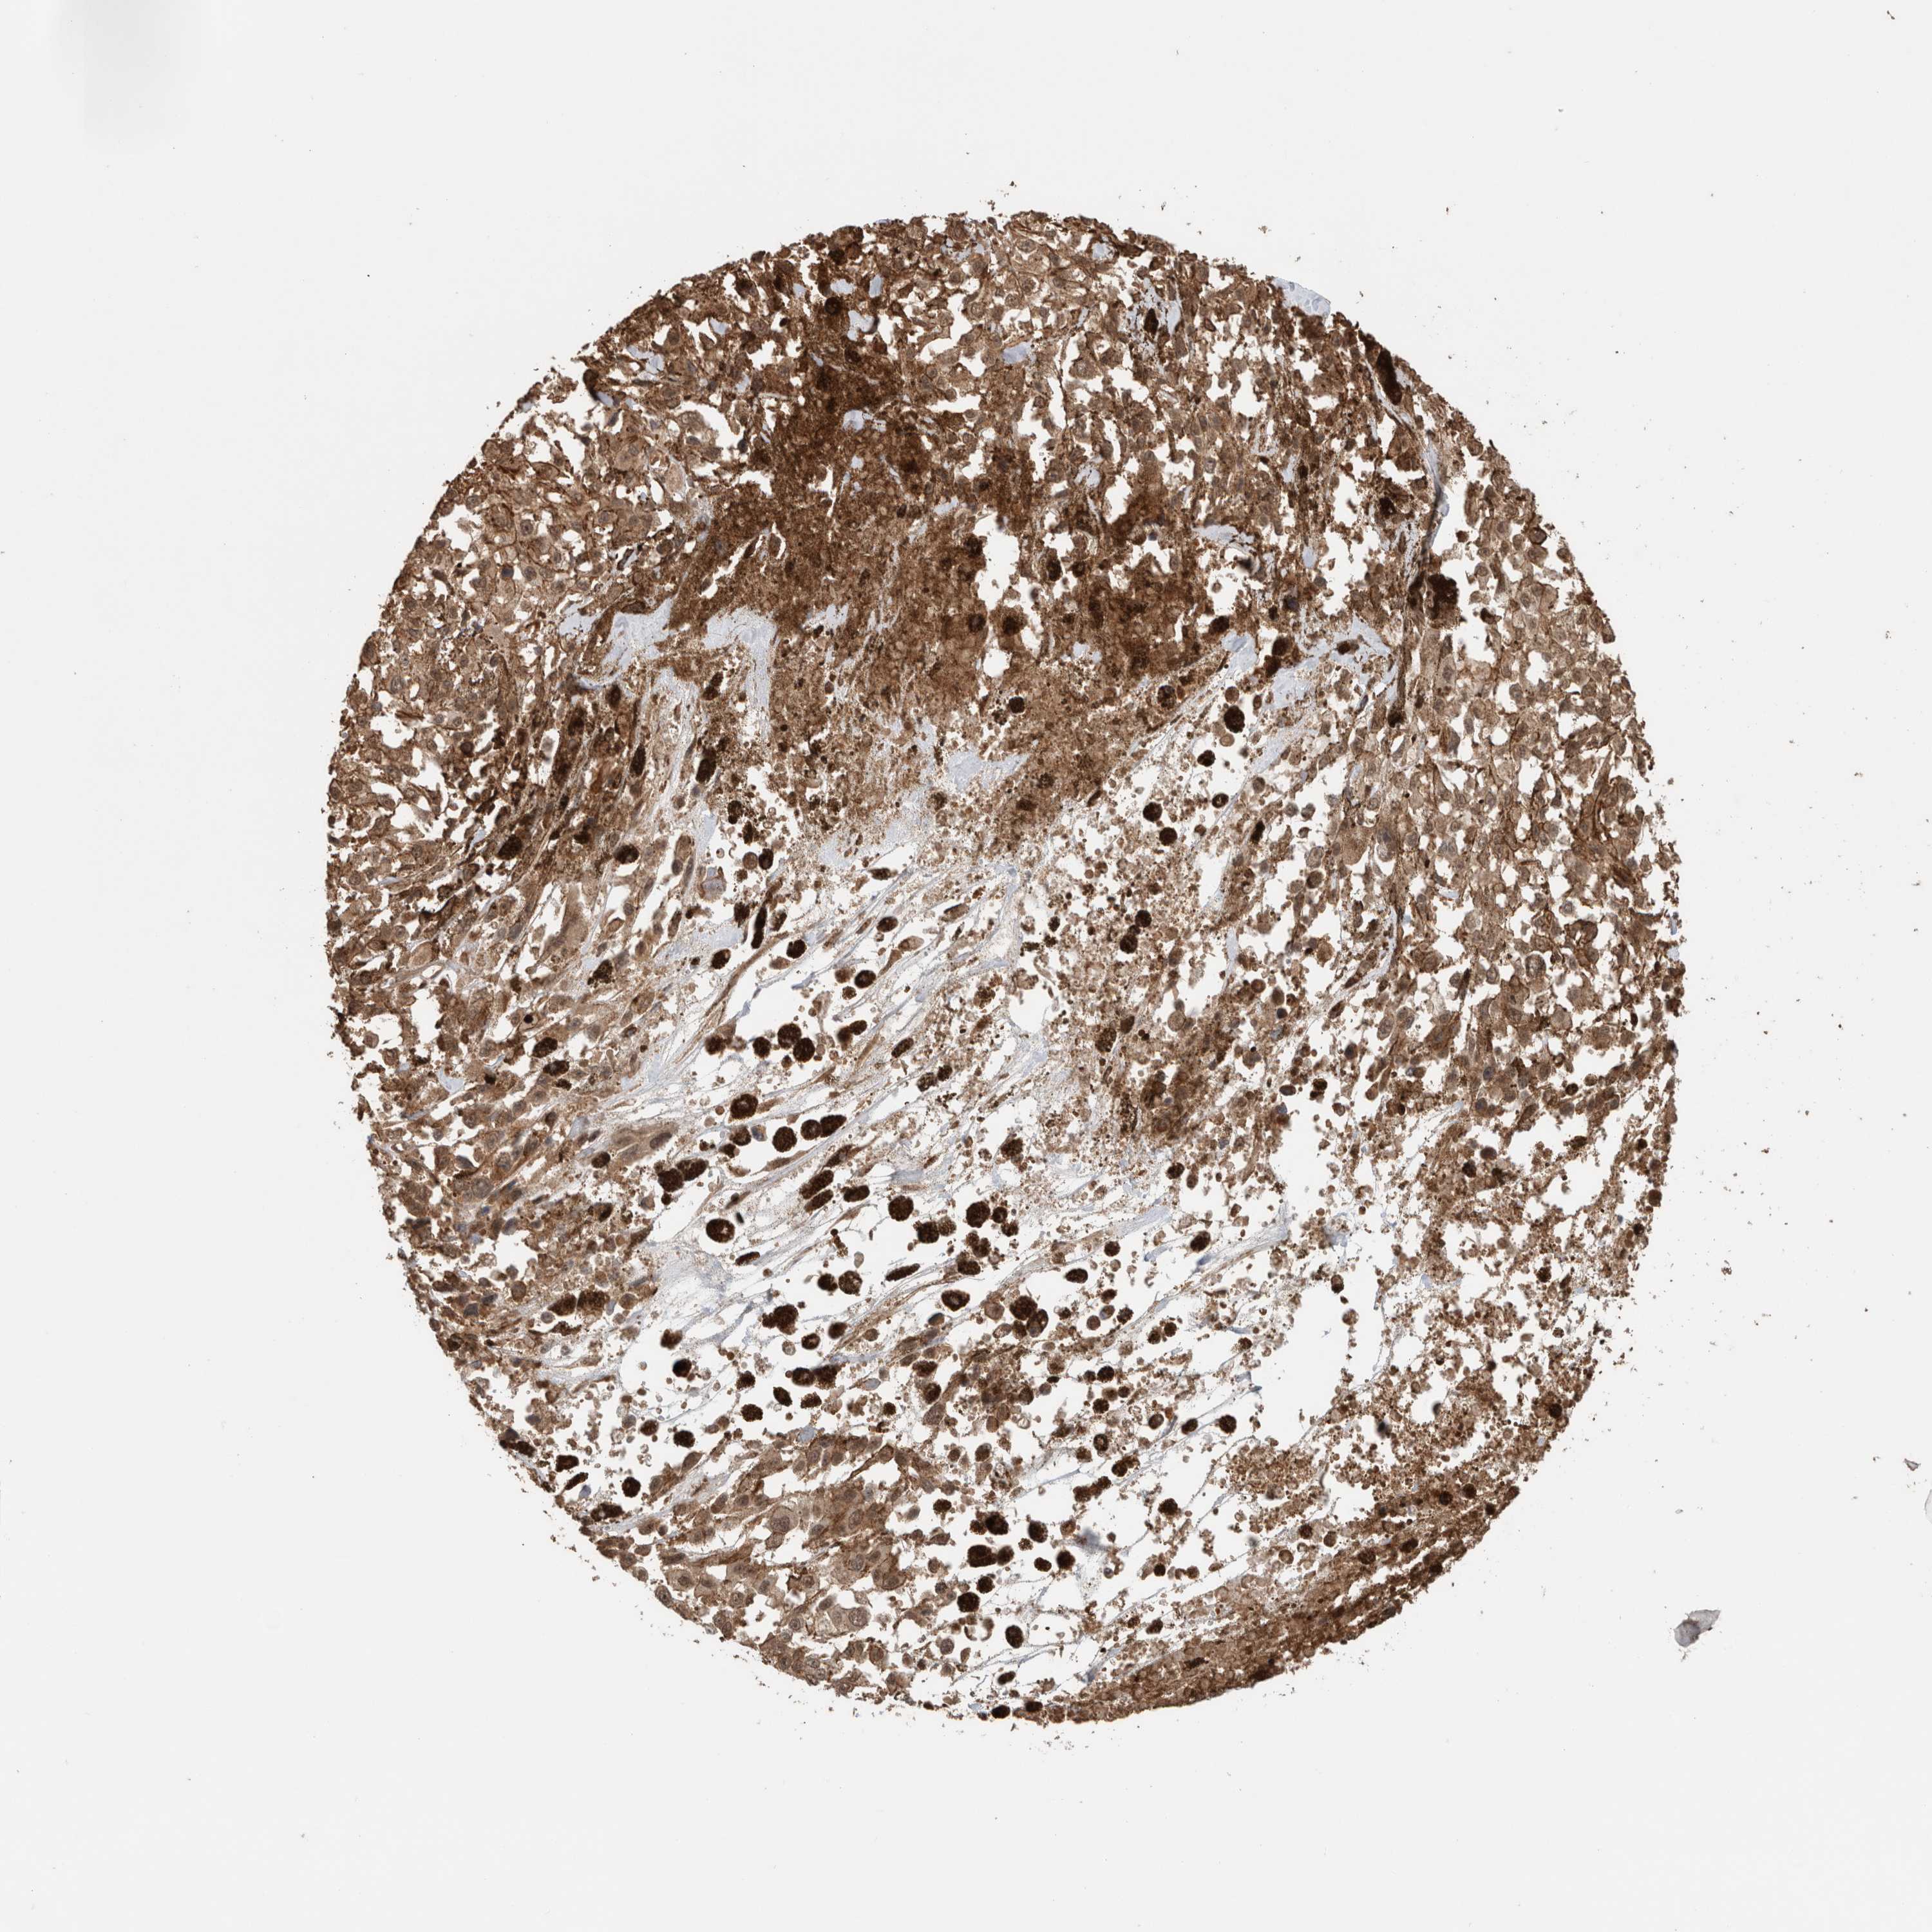

MELANOMA - Protein expressioni

A mouse-over function shows sample information and annotation data. Click on an image to view it in a full screen mode. Samples can be filtered based on level of antibody staining by selecting one or several of the following categories: high, medium, low and not detected. The assay and annotation is described here.

Note that samples used for immunohistochemistry by the Human Protein Atlas do not correspond to samples in the TCGA dataset.

Antibody stainingi

Antibody staining in the annotated cell types in the current human tissue is reported as not detected, low, medium, or high, based on conventional immunohistochemistry profiling in selected tissues. This score is based on the combination of the staining intensity and fraction of stained cells.

Each image is clickable and will lead to virtual microscopy that enables deeper exploration of all samples and also displays staining intensity scores, fraction scores and subcellular localization as well as patient and tissue information for each sample.

Antibody HPA024046

Antibody HPA024503

Antibody HPA024772

Staining

High

Medium

Low

Not detected

Intensity

Strong

Moderate

Weak

Negative

Quantity

>75%

75%-25%

<25%

None

Location

Nuclear

Cytoplasmic/membranous

Cytoplasmic/membranous,nuclear

Malignant melanoma, NOS

Malignant melanoma, Metastatic site